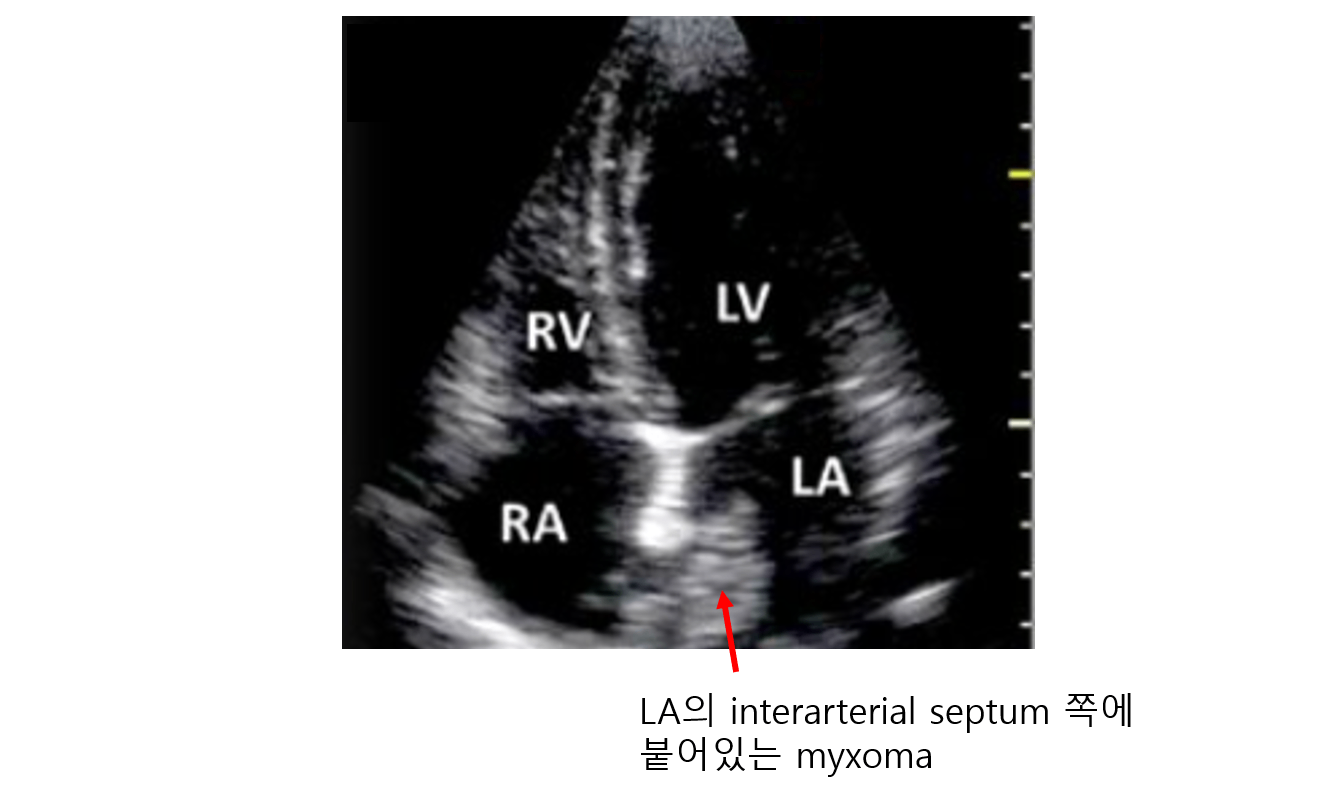

1. 점액종(myxoma)

(1) 원발성(primary) 심장 종양 중 m/c, 양성 종양

(2) 젤리같은(gelatinous) 질감: Glycosaminoglycan이 대량 함유

(3) 주로 interatrial septum에서 생성됨

3) 진단: 경흉부/경식도심초음파 → CT/MRI